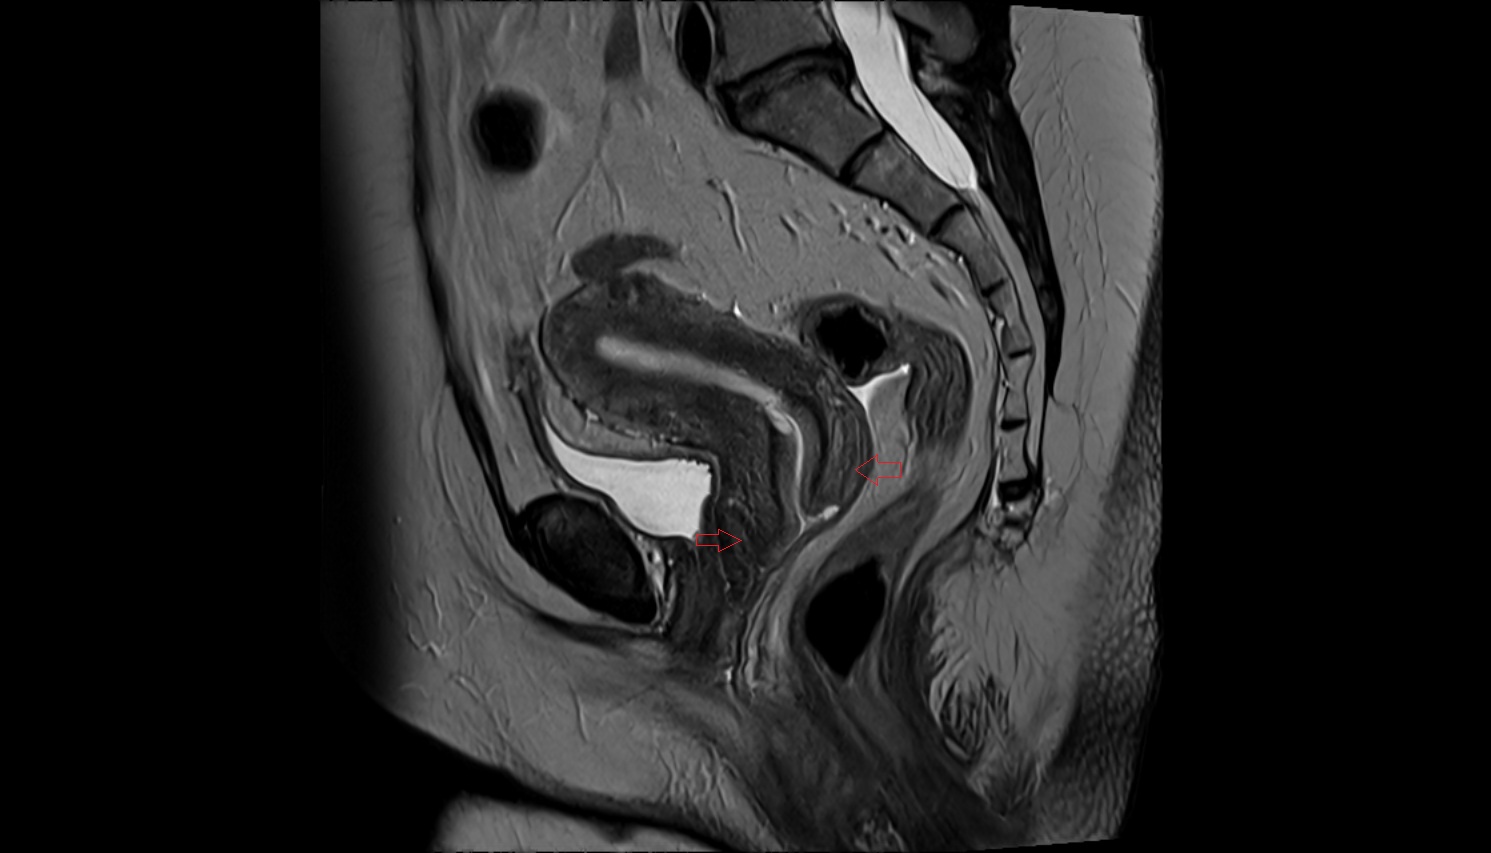

- Uterus

- Body of uterus

- Fundus of uterus

- Cervix of uterus

- Isthmus of uterus

- Vagina

- Fornix of the vagina

- Endometrium of uterus

- Myometrium of uterus

- Perimetrium of uterus

- Junctional zone of uterus

- Rectum

- Urinary bladder

- Vesicouterine pouch

- Rectouterine pouch (pouch of Douglas)